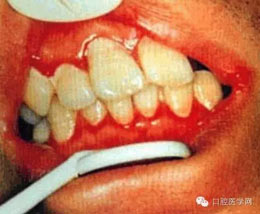

(三)齦炎: 齦緣呈一條火紅色帶或口腔無其他異常而牙齦呈局灶性腫。

(四)壞死性齦炎:為局限的或普遍的潰瘍形成,牙間乳頭破壞,并伴有纖維蛋白性壞死。